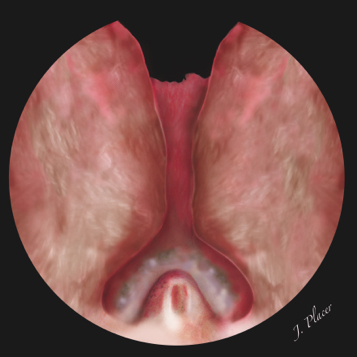

En nuestro centro comenzamos la enucleación prostática practicando una pequeña incisión transversa craneal al verumontanum (Figura 4). La incisión se extiende bilateralmente hasta llegar al borde medial de ambos lóbulos apicales y se profundiza en el adenoma hasta identificar la cápsula prostática. La superficie interna de la cápsula prostática se caracteriza por ser ligeramente brillante, por tener un color blanquecino-nacarado y por presentar pequeños vasos sanguíneos que discurren de forma transversa por su superficie. Durante la realización de esta incisión es frecuente identificar los conductos eyaculadores seccionados. La próstata suele estar bastante vascularizada a este nivel y en ocasiones la visión endoscópica no es buena por sangrado. Aunque la práctica sistemática de esta incisión al inicio de la cirugía no ha sido descrita por otros autores, creemos que su realización al comienzo de la cirugía ayuda a marcar y respetar el límite caudal de la enucleación, protegiendo de esta manera el esfínter externo. Además su realización inicial facilita la posterior disección de los lóbulos apicales.

Figura 4. Incisión transversa practicada de forma proximal al verumontanum